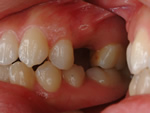

乳歯晩期殊なし

永久歯が前出しない

→

乳歯と永久歯を抜歯し

インプラント埋入